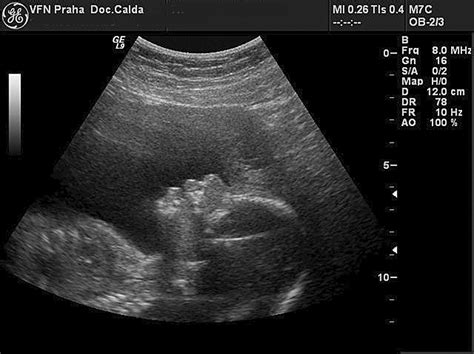

Počas tehotenstva sú ženy podrobované špeciálnym vyšetreniam z krvi a moču, ktoré slúžia na monitorovanie zdravotného stavu matky a odhalenie prípadných infekcií či iných abnormalít. Súčasťou štandardnej starostlivosti sú tiež tri ultrazvukové sledovania. Tieto vyšetrenia umožňujú sledovať rast a vývoj plodu, posúdiť jeho anomálie a zaznamenať obrazovú dokumentáciu.

Pre poistenky VšZP existuje ďalšia výhoda - počas tehotenstva majú nárok aj na štvrtý ultrazvuk, ktorý im prepláca poisťovňa. Táto dodatočná možnosť umožňuje ešte podrobnejšie sledovanie vývoja dieťaťa a poskytuje rodičom cenné vizuálne informácie.